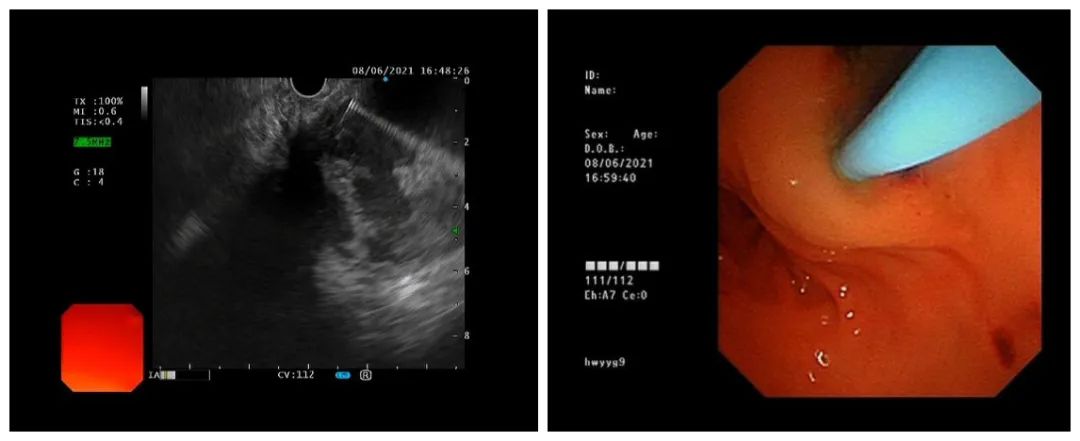

为引流囊肿和解除压迫症状,王东为小熙进行了超声胃镜下胰腺巨大假性囊肿引流术,术中抽出了大量稠厚的咖啡色坏死液体。

针对小熙的情况,常规方法即放置支架无法充分引流稠厚的囊液,加之囊肿较大,其底部引流不好的话,易继发感染。因此,为了引流充分和冲洗囊肿,王东主任在超声内镜引导下,穿刺针避开血管穿刺进入囊肿,置入导丝,沿导丝置入鼻囊肿引流管。20分钟左右,手术顺利结束。

超声内镜引导下穿刺引流 (左图)

引流管穿过胃壁进入囊肿(右图)